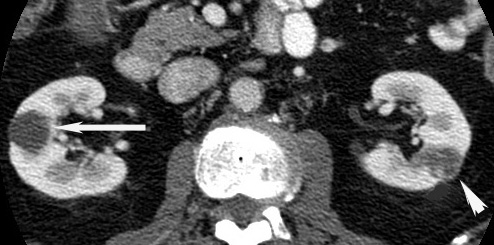

Simple Renal Cyst Right Kidney/ Cancer left kidney

Renal Cyst (arrow).

Renal carcinoma (arrowhead).

Contrast the clear well defined fluid filled cyst, from a cancer which appears as a cystic mass with enhancing tissue within.